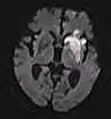

Diffusion weighted (DWI)ConventionalDWIMeasure of Brownian motion of water molecules.[59] High signal within minutes of cerebral infarction (pictured).[60]

Apparent diffusion coefficientADCReduced T2 weighting by taking multiple conventional DWI images with different DWI weighting, and the change corresponds to diffusion.[61] Low signal minutes after cerebral infarction (pictured).[62]